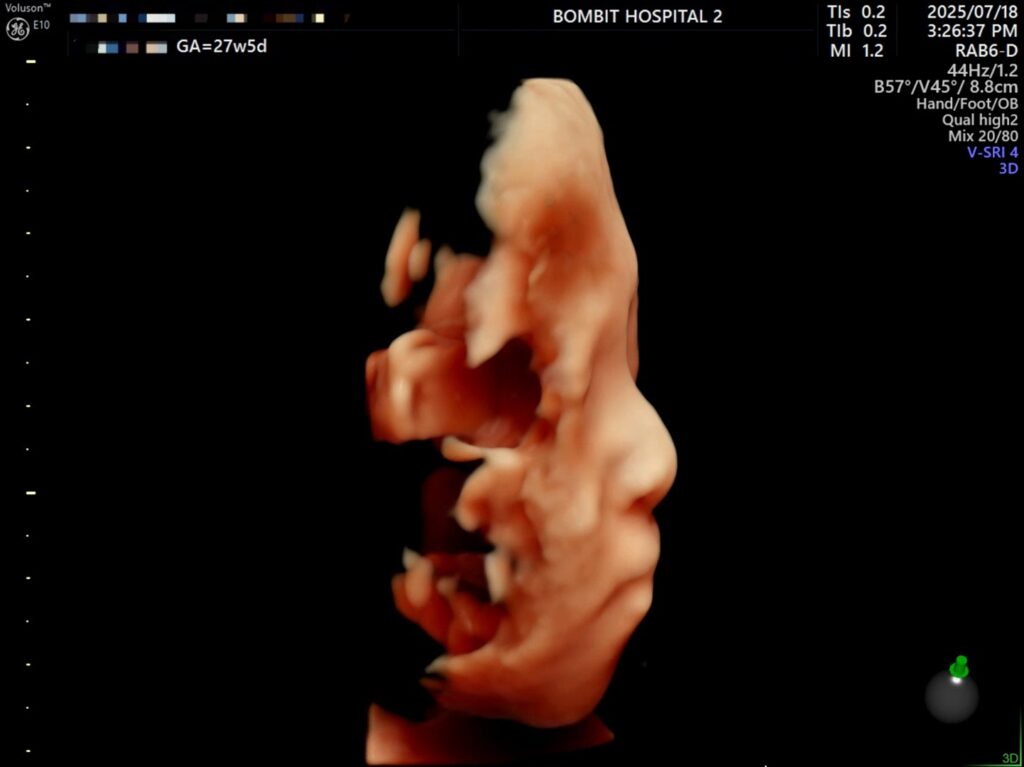

입체초음파로 본 단비는 처음에 완전히 엎드려있었다. 바닥을 향해 엎드려서 얼굴을 파묻고 귀 밖에 안 보여줌.. ㅜㅜ

초코우유도 못 먹는 몸인지라, 초음파실 샘이 권유한대로 물을 마시고 로비를 한 3바퀴정도 힘차게 걷고 나서 다시 초음파를 봤다. 단비가 여전히 엎드려있길래 선생님이 배의 특정 부분을 두드리셨는데(단비 미안).. 단비가 움직였다!

그렇게 다행스럽게도 단비 얼굴을 볼 수 있게 되었다.